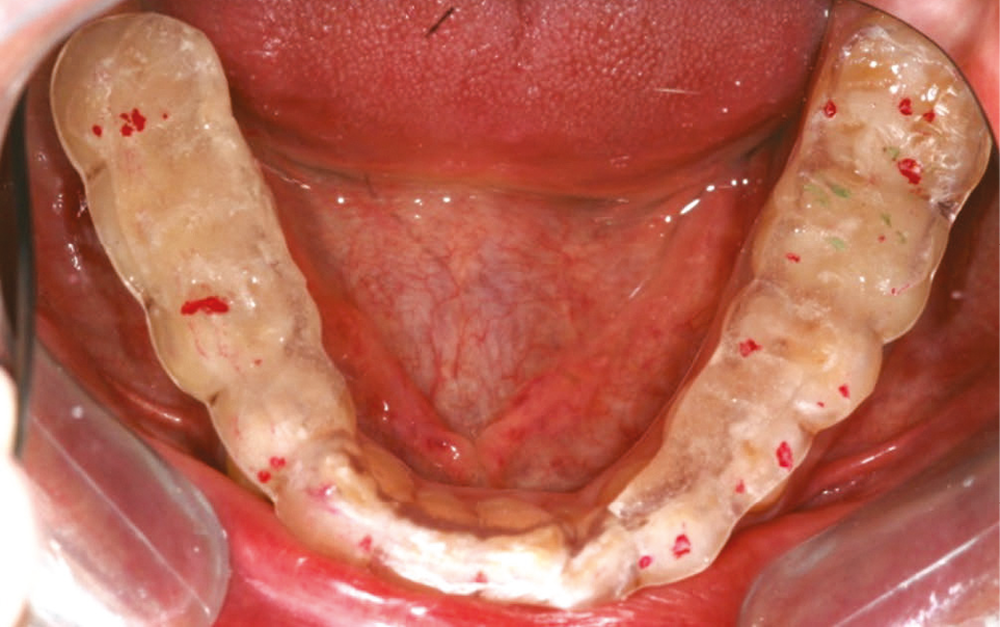

Nous considérerons que le dépistage de DTM avant réhabilitation implanto-portée concerne tous les patients ayant perdu au minimum toutes les molaires d’un quadrant, y compris la dent de sagesse. Il s’agit donc des patients présentant des édentements terminaux, dits de classes I et II de Kennedy (fig. 1a-b). Seront également concernés les patients présentant plus largement une perte de calage postérieur (absence de contacts molaires antagonistes).

De plus, nous proposons d’y inclure également les patients déjà réhabilités par une prothèse amovible partielle. En effet, quelle que soit la qualité de la prothèse, il est fréquent d’observer une perte de hauteur prothétique liée à l’usure et/ou à l’enfoncement, ce qui provoque une perturbation de la courbe de Spee et une compression articulaire.